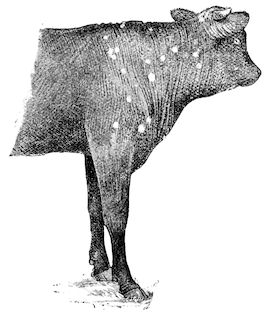

Fig. 1.—Rachitis in a young goat.

Rachitis is a disease of youth, and is common both to the human species and to all domestic animals. It is characterised by irregularities in development and by imperfect consolidation of the bones. The boundary between rachitis and osseous cachexia is difficult to define and in fact at the present moment the two diseases can scarcely be defined with exactitude. Rachitis again is often complicated with softening of the bones, disease of the limbs, arrested development, etc., but it must not be forgotten that although the irregularities in ossification and development of the skeleton are the symptoms most striking to the eye, they do not stand alone, and that from the point of view of development all the tissues, including the muscles, are more or less affected and that most of the physiological functions such as digestion and the secretion of urine are deranged.

Symptoms. The onset is absolutely insidious and the diagnosis of rachitis is never made until nutrition has long been abnormal.

This disturbance of nutrition is revealed by irregularity and abnormality in appetite, by difficulty in rising and moving about, and by the animals lying down for long periods. The subjects are feeble, sluggish and badly developed.

Next supervenes the second phase characterised by deformity of bones. This is of two kinds—deformity in the neighbourhood of joints (deformity or enlargement of the epiphyses) and deformity of the diaphyses. The former results from irregularity in ossification of the articular cartilages. The latter is followed by loss of rigidity in the bones of the limbs which, under the influence of the body weight and of muscular contraction, bend in different directions.

The bones appear of increased thickness principally towards the 6articulations. The latter are deformed, and on palpation are found to be surrounded by uneven and irregular growths.

The front limbs are distorted. In young pigs, lambs, and less frequently in foals, calves and dogs, the jaws become deformed, and mastication is rendered difficult.

The vertebral column may also be affected, and lordosis (bending downwards of the back) or skoliosis (lateral bending of the back) is somewhat frequent.

Cyphosis, or upward bending of the back, seldom occurs, and when seen, sometimes results from disease other than rachitis.

General development is always interfered with and the young creatures are generally dwarfed.

The digestive apparatus is disordered, the appetite is irregular and sometimes depraved, while indigestion, gastritis, and enteritis are not exceptional. Physiological and pathological research has shown that the quantity of phosphoric acid eliminated in twenty-four hours in a rachitic child is double the quantity passed by a healthy infant. The amount of urea in the urine (which is a criterion of nutrition, and usually varies in proportion to the amount of food ingested) is, on the contrary, diminished even when highly nitrogenous food is given, thus suggesting diminution in nutrition.

Lesions. The lesions are represented by abnormal and irregular thickening around the interarticular cartilages. The cartilage is thickened, compressible, very spongy and without regular ossification. Diffused periostitis exists principally towards the extremities of the bone. Beneath the periosteum the surface of the bone appears rough and softened. On section the medullary canals are seen to be enlarged and filled with marrow of a gelatinous character. The Haversian canals are dilated, and the entire tissue appears very vascular. Chemical analysis proves that the mineral constituents of the bone, particularly the phosphates, have diminished by one-half; the organic constituents on the other hand are increased in a similar ratio, but the ossein is abnormal. Ossification has, in a word, been incomplete.

7Diagnosis. Diagnosis presents no difficulty except in the early stages before deformity has occurred.

Rachitis can scarcely be mistaken for any other condition except perhaps infectious rheumatism, but the rapid course of the disease in the latter case, the persistence of fever and the swelling of the joint cavities sufficiently differentiate the conditions provided care is exercised.

Prognosis. From an economic point of view the prognosis is very grave for if the lesions are extensive there is nothing to be gained by keeping the animal.

Treatment. Treatment differs very little, whether the animals are still being suckled or have been weaned. In the former case it is necessary to improve the quality and chemical constitution of the mother’s milk by giving food, richer both in mineral salts and in nitrogenous material.

Cooked grains, milk, and forage of good quality should be given freely. When the mothers are exhausted and anæmic it is better to feed the little animals artificially or to change them to a foster-mother. Those already weaned should be given good rich milk, eggs, boiled gruel, and drugs, such as the phospho-chlorate of lime, 1 to 1½ drachms per day (for a calf); lacto-phosphate of lime, 1 to 1½ drachms; bi-phosphate of lime, 1 drachm, or simply ordinary phosphate of lime. Oil containing 1 per cent. of dissolved phosphorus may be given in doses of 1 to 2½ drachms, according to the size of the calves, but its use calls for much care, and it should only be given for alternate periods of a fortnight. The glycerophosphates are not very active. Beef meal in doses of 6 drachms to 1½ ounces and chloride of ammonium in doses of 30 to 60 grains have also been used advantageously. The above drugs, but particularly the bi-phosphate of lime and chloride of ammonium, stimulate nutrition and diminish the quantity of phosphoric acid eliminated.